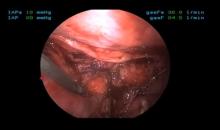

This video demonstrates the technical strategy for the resection of a complex posterior mediastinal cyst.